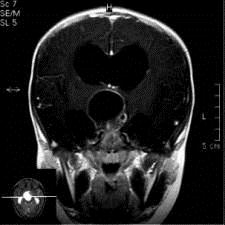

问题 病历摘要:??患者女性,6岁,半年来感觉视力模糊,近10天出现反复头痛,间有恶心呕吐,精神转差,查体:神志清楚,身高90cm,体重25Kg,血压90/55mmHg,右眼视力4.6,左眼视力4.8,双侧视乳头水肿,颈软,伸舌居中,四肢肌张力正常,肌力5级,双侧Babinski征(-)。 患者具有下列那些表现,可以诊断抗利尿激素分泌不当综合征?